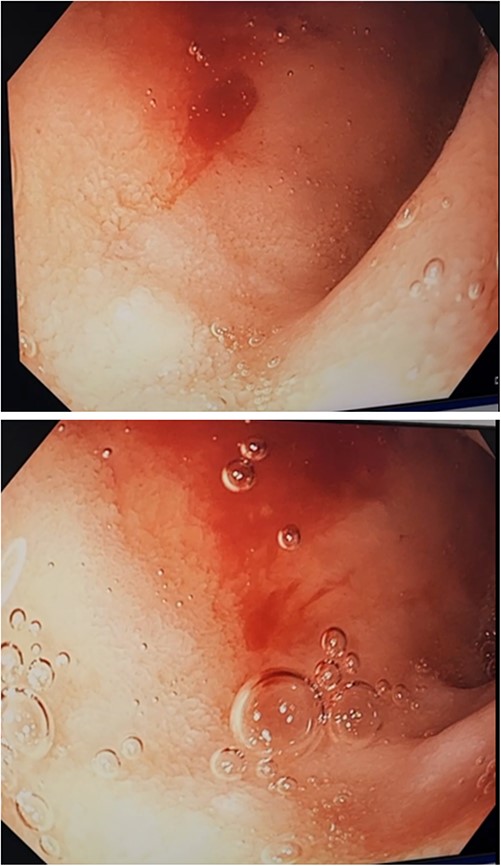

Three days after initial gastroscopy she developed further melena and anaemia, requiring additional PRBCs. She underwent a second gastroscopy, which demonstrated a lesion consistent with a DL at the junction of D1/D2 which was actively bleeding from an exposed vessel (Fig. 3). Haemostasis was achieved with thermocoagulation and adrenaline injection (Fig. 4). The melena resolved and haemoglobin remained stable. The remainder of her admission and 2-month follow-up were unremarkable.

Second gastroscopy – active arterial bleeding at D1/D2 from small mucosal defect without surrounding ulceration.

Second gastroscopy – successful haemostasis of actively bleeding duodenal DL with thermocoagulation and adrenaline injection.